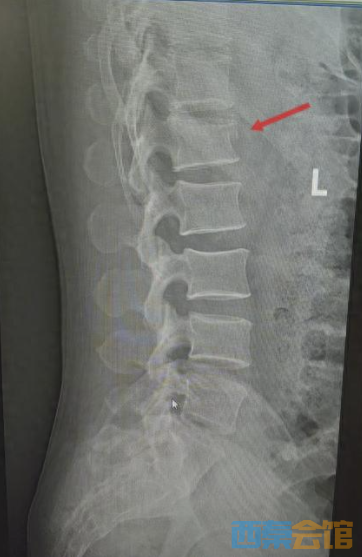

湖北日报讯(记者汪菁华、通讯员林国山)近日,45岁的周先生(化姓)从约3米高处意外坠落,臀部首先着地,当即感到腰骶部剧烈疼痛。情况紧急,他随即被送往武汉大学泰康临床学院/泰康同济(武汉)医院创伤外科,诊断为腰1椎体压缩性骨折。

患者伤情影像

针对伤情,武汉大学泰康临床学院/泰康同济(武汉)医院创伤外科主任张俊与骨科主任姚士军迅速组建救治团队,对影像学资料进行详细研判,结合患者高血压病史,综合评估骨折稳定性及神经受压风险。经讨论,团队决定采用经皮椎弓根钉棒复位内固定术。该术式属微创范畴,可在实现骨折复位固定的同时,最大限度减少对腰背部肌肉及软组织的损伤,有利于患者术后早期功能锻炼及快速康复。